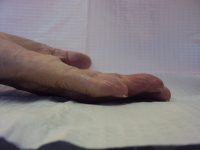

Clinical Example: Dupuytren Distal Interphalangeal Joint Needle Fasciotomy

Dupuytren contracture usually involves the metacarpophalangeal and proximal interphalangeal joints, but occasionally affects the distal interphalangeal joints. This is usually accompanied by proximal interphalangeal joint involvement. This is almost always a lateral rather than a central cord, and may present as a spiral cord, the neurovascular bundle superficial just proximal to the distal interphalangeal joint.

The functional impact of this is that it contributes to the fingertip catching on things like a hook. Isolated interphalangeal joint contractures in the context of hyperextensible metacarpophalangeal joints allow patients to defer evaluation until the contracture is severe.

The most common method of treating this is with fasciectomy, but needle fasciotomy may be effective. Collagenase has been used for this, but is an off-label application.

As with needle release or collagenase treatment of the proximal interphalangeal joint, recurrence is expected: these minimal procedures should be considered a temporizing step with expectations of partial improvement.

The following are examples of percutaneous needle fasciotomy for a variety of contractures involving the distal interphalangeal joint. Portals proximal and/or distal to the distal interphalangeal joint flexion creases are used, some bilaterally.

These are presented to illustrate the diversity of even this subset of Dupuytren disease. None had prior treatment.